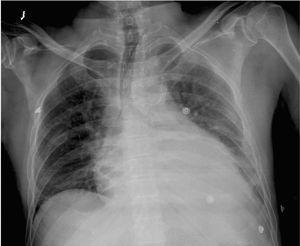

Varón de 56 años de edad, con antecedentes de enfermedad coronaria (infarto agudo de miocardio inferior en 1985, enfermedad de coronaria derecha con tratamiento médico), diabetes mellitus tipo 2 insulinodependiente, hipertensión arterial, ulcus gástrico y bulbar secundario a antiinflamatorios y bursitis séptica estafilocócica cuatro meses antes. Dos semanas antes del ingreso comienza con dolor epigástrico irradiado a región precordial, que aumenta con la inspiración, disnea de moderados esfuerzos y sensación distérmica. A su ingreso presenta tensión arterial sistólica 80 mmHg, frecuencia cardíaca 100 lpm, saturación de O2 con oxigenoterapia 90%, temperatura de 39 ºC e ingurgitación yugular; siendo el resto de la exploración física anodino. En la analítica destaca leucocitosis de 22.640 con 85,5% de polimorfonucleares, troponina 2,43 ng/ml. Electrocardiograma en ritmo sinusal a 95 lpm, elevación segmento ST de 2 mm en V2, mínima elevación en resto de precordiales, descenso PR en V5 V6 y II (fig. 1). Radiografía de tórax con cardiomegalia y discreto pinzamiento del seno costofrénico izquierdo (fig. 2). Se practica ecocardiograma transtorácico y transesofágico que muestran ventrículo izquierdo normal con acinesia inferoposterobasal e hipoquinesia leve lateral, derrame pericárdico severo (20 mm posterior, 7 mm anterior), colapso diastólico de aurícula derecha, leve dilatación de ventrículo derecho, vena cava inferior dilatada (25 mm) con colapso inspiratorio disminuido.

Figura 2. Radiografía posteroanterior de tórax; cardiomegalia y borramiento costofrénico izquierdo.